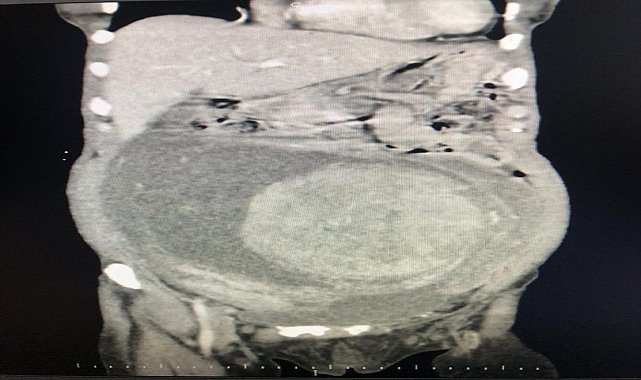

Tokat Devlet Hastanesi'nde görevli Genel Cerrahlar Operatör Doktor Ahmet Topcu ve Orkun Subaşı, Hicran Işık tarafından gerçekleştirilen başarılı ameliyatla, Işık'ın yumurtalıklarından 30x25 santim boyutlarında ve 6 kilogram ağırlığında kitle çıkarıldı. Ameliyatın ardından Hicran Işık sağlığına kavuştu.